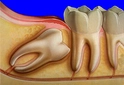

Diş Çekiminden Sonra Kök Kalması Ne Anlama Gelir?Diş çekimi, diş hekimliğinde sıkça başvurulan bir tedavi yöntemidir. Dişin tamamen çıkarılması gerektiğinde, genellikle dişin kök kısmı da dahil olmak üzere dişin tüm bileşenleri çekilir. Ancak bazı durumlarda, dişin kök kısmı çene kemiğinde kalabilir. Bu durum, çeşitli sebeplerle ortaya çıkabilir ve genellikle komplikasyonlar doğurabilir. Bu makalede, diş çekiminden sonra kök kalmasının anlamı, sebepleri, sonuçları ve tedavi yöntemleri detaylı bir şekilde ele alınacaktır. Kök Kalmasının SebepleriDiş çekiminden sonra kök kalmasının birkaç nedeni vardır:

Kök Kalmasının SonuçlarıDiş çekiminden sonra kök kalması, bazı olumsuz sonuçlara yol açabilir:

Tedavi YöntemleriDiş çekiminden sonra kalan kökün tedavisi için çeşitli yöntemler bulunmaktadır: